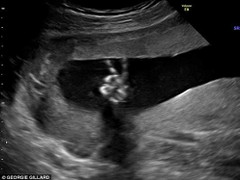

Một gia đình người Anh đã hết sức ngạc nhiên khi nhận được kết quả siêu âm cho thấy hình ảnh thai nhi biết "tạo dáng chữ V" trong bụng mẹ.